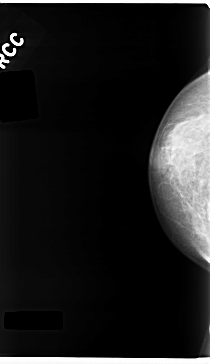

C_0237_1.RIGHT_CC

RIGHT_CC LINES 4720 PIXELS_PER_LINE 2720 BITS_PER_PIXEL 12 RESOLUTION 50 NON_OVERLAY